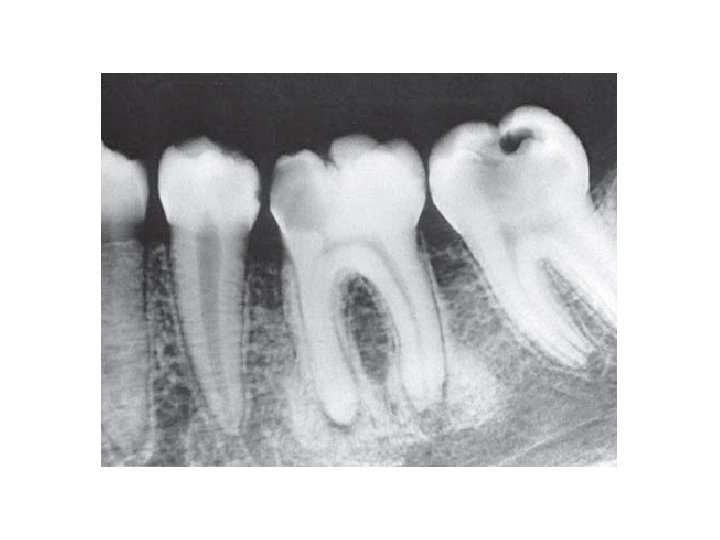

Wurzelbehandlung

Vor der Wurzelbehandlung Nach der Wurzelbehandlung